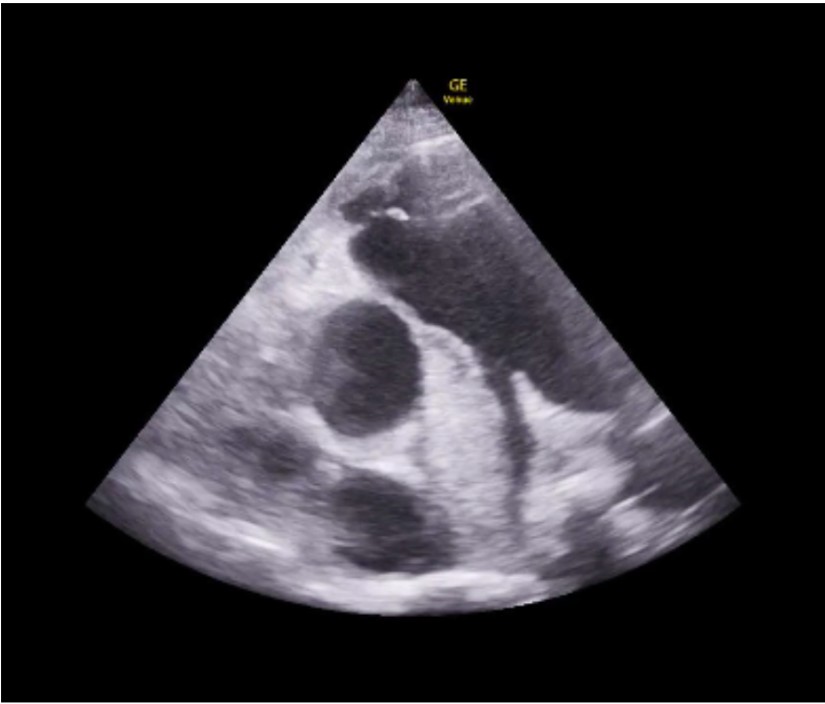

Our patient is a 42-year-old male with a medical history of insulin-dependent diabetes (IDDM), hyperlipidemia, and end-stage renal disease (ESRD) on dialysis who makes urine two times per week, who initially presented to the emergency department after having purulent penile discharge that started about twelve days prior, now with suprapubic abdominal pain and fullness for the past several days. He was afebrile and vital signs showed heart rate of 97 beats per minute, blood pressure of 79/57 mmHg, respiratory rate of 18 breaths per minute, and oxygenation of 97% on room air. On exam, the patient had suprapubic abdominal tenderness without peritoneal signs. Patient deferred rectal exam. On laboratory testing, the patient had a white blood cell count of 20.5K. Urinalysis showed greater than 100 white blood cells, 84 red blood cells, many bacteria, and was negative for nitrates. Due to concern for infection and possible sepsis, intravenous vancomycin and cefepime were initiated in the ED. Straight catheterization was initially attempted without any return of urine. Point of care bladder ultrasound was done to evaluate bladder volume for urinary retention. It revealed a hyperechoic mass extending into the bladder consistent with a large prostatic abscess (PA), though bladder volume was approximately 68 mL, and foley catheter was later placed. (Figure 1) A computed tomography (CT) scan of the abdomen and pelvis with intravenous contrast demonstrated multiple rim-enhancing fluid collections which measured collectively as 5.3 x 5 x 5.6 cm with fat stranding over the prostate. Urology was consulted, and the patient was admitted to the hospital. He underwent a transurethral unroofing of the PA with urology the next day, and urine and blood cultures grew Escherichia coli.

In our patient’s case, the use of point of care transabdominal ultrasound to investigate the patient’s sensation of urinary retention led to the preliminary diagnosis of PA. On ultrasound, in both the transverse (1) and longitudinal (2) view, a multiloculated abscess is seen, indicated by the hypoechoic areas, measuring approximately 5 x 5 x 5 cm. CT scan was then done to confirm and better characterize the abscess, urology was consulted, and ultimately the patient had definitive treatment with antibiotics and transurethral unroofing of the abscess in the operating room.

Figure 1: Transverse view of the bladder with prostate abscess.

Figure 2: Longitudinal view of the bladder with prostate abscess.